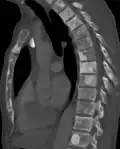

Sclerosis of the bones of the thoracic spine due to prostate cancer metastases (CT image) -

Sclerosis of the bones of the thoracic spine due to prostate cancer metastases (CT image)